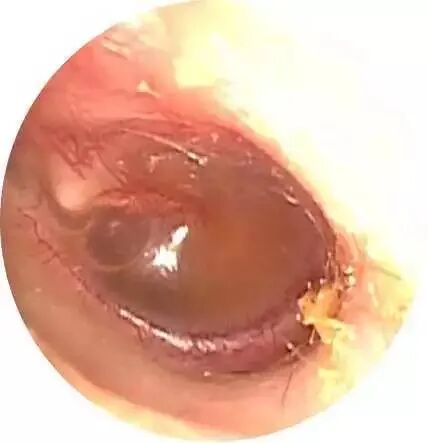

3、真菌性外耳炎

以曲霉菌、青霉菌及念珠菌为主的常见真菌侵入人的外耳道,引起外耳道真菌病。

症状和体征

多数可有耳痒,耳闷,部分可有耳鸣、听力下降。合并感染时可引起外耳道肿胀、疼痛和流脓。

治疗

及时至医院就诊,清除外耳道内真菌痂皮和分泌物。外耳道表面涂上抗真菌药物。同时也可用制霉菌素喷于外耳道。尽量保持外耳道干燥。